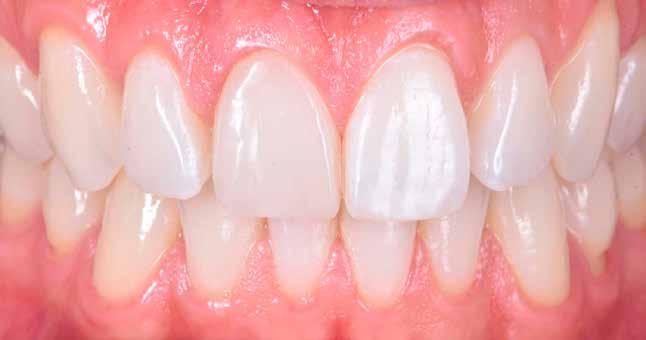

A pácienst 21 nap (14–15. ábrák) és 12 hónap (16. ábra) után ismét ellenőrizzük, hogy értékeljük az esztétikai eredményt a forma és a szín tekintetében.

13. ábra: Az UL1 emulálása polírozás közben. – 14. ábra: A helyreállítás 21 nap után.

15. ábra: A helyreállítás 21 nap után.

16. ábra: A helyreállítás 12 hónap után.